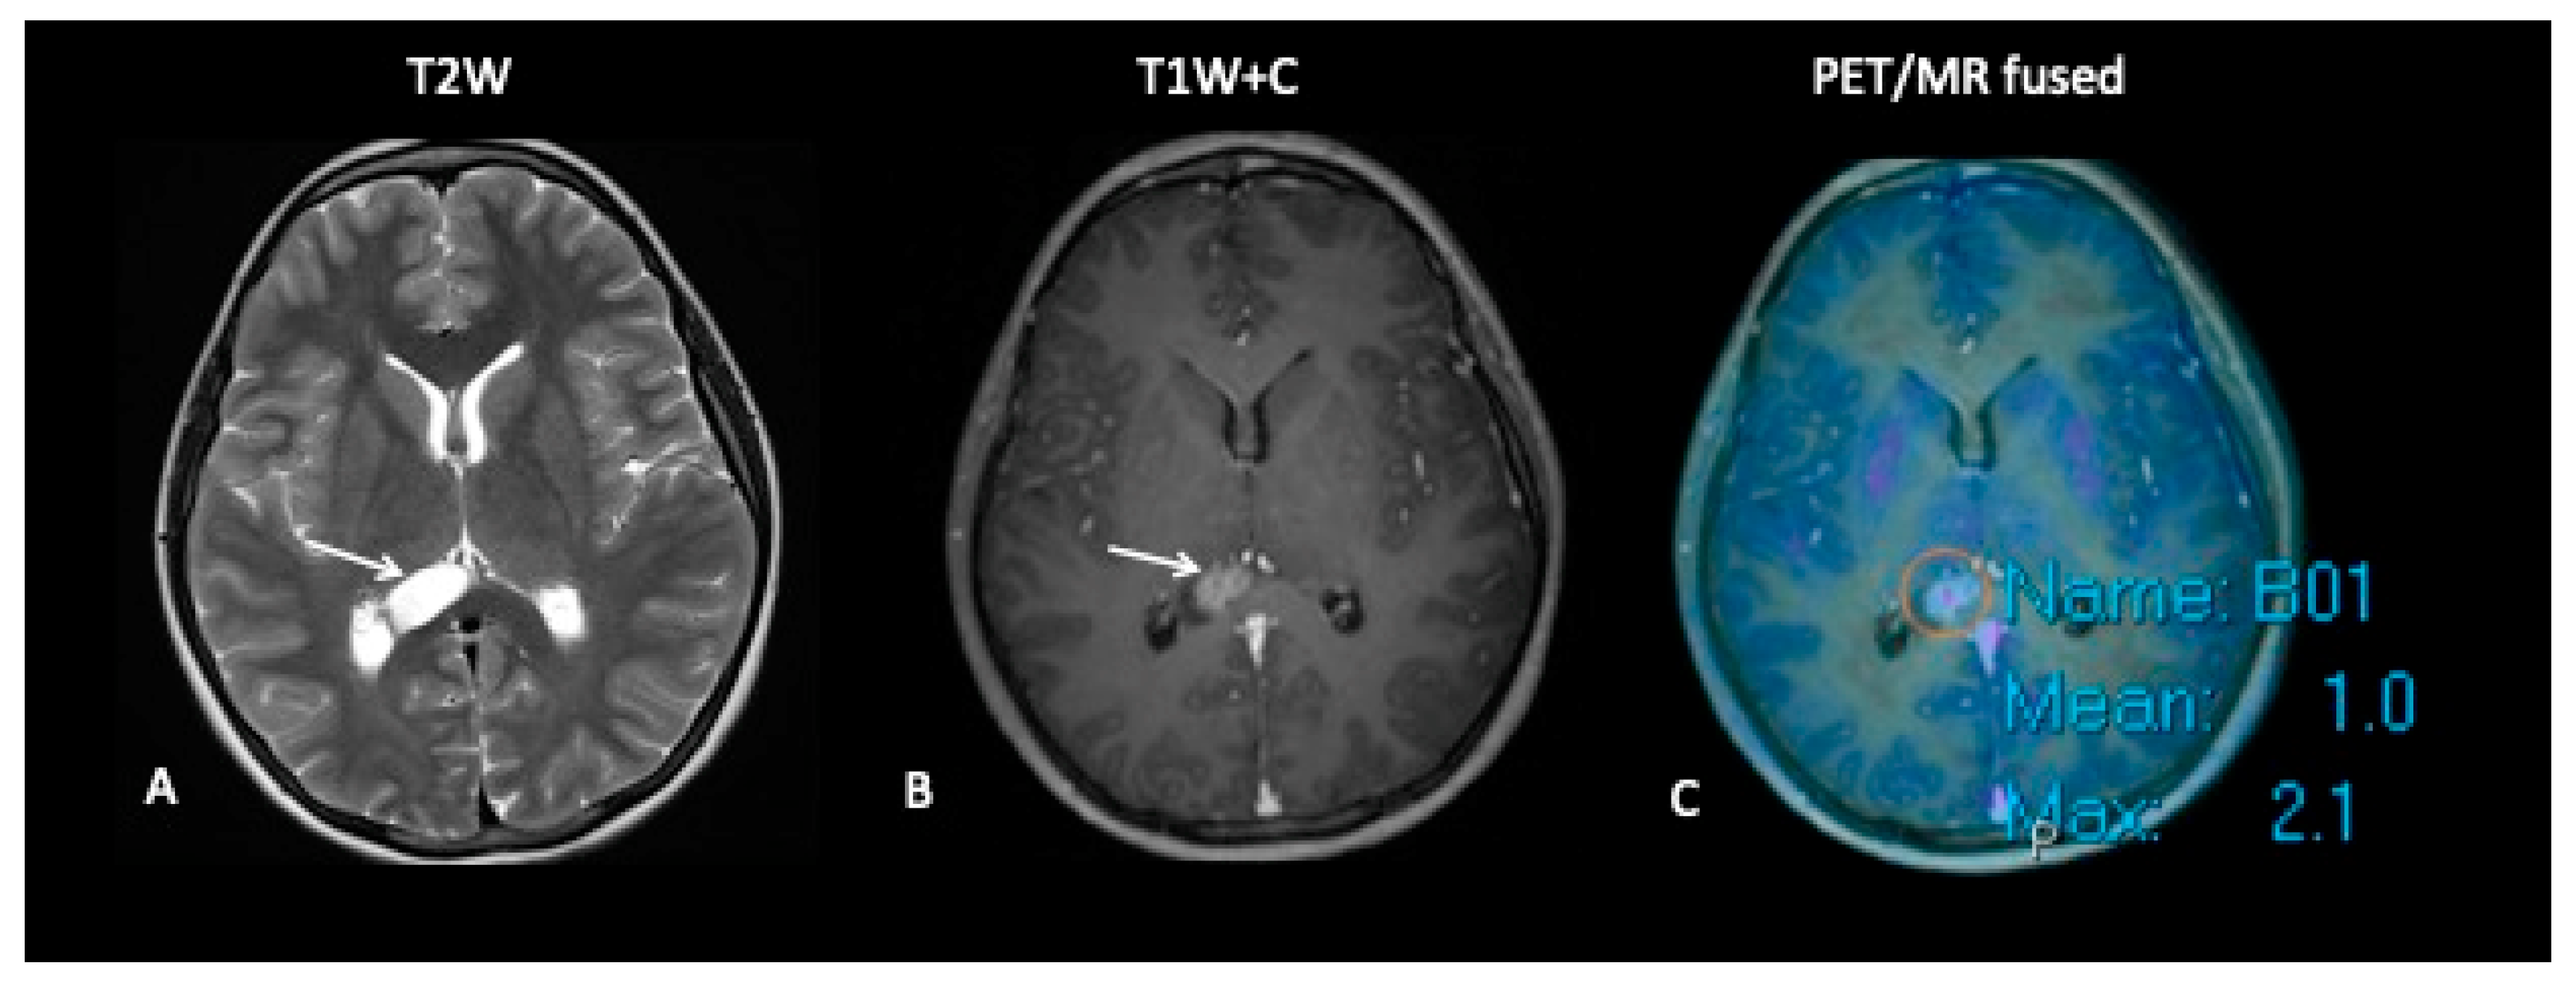

- Patient 8: Suspicion of Transformation

A 15-year-old female with known low-grade glioma during routine surveillance was noted to have developed a large lesion in the corpus callosum. This occurred 7 years after her initial diagnosis of an optic pathway tumour. The MRI scan raised the possibility of malignant transformation to high-grade glioma. FDOPA (Figure 11) discounted the possibility of transformation as the FDOPA uptake within the corpus callosal lesion was low intensity, unlike that seen in high-grade gliomas.

Figure 11.

MRI demonstrates an expansile lesion in the right aspect of the splenium (A), which demonstrates heterogenous enhancement (B), suspicious for malignant transformation. However, FDOPA (C) did not demonstrate increased uptake, and the lesion was considered low grade.